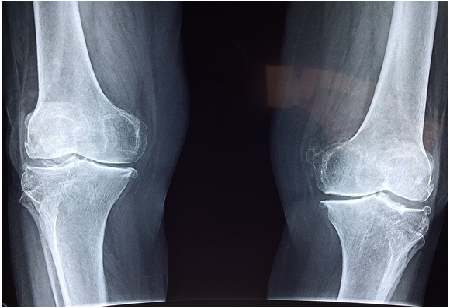

Physical impairments are the most apparent effects of a serious injury. Losing the ability to perform basic bodily functions is one that not only has an adverse effect on a person’s mobility, but it will also rob that person of opportunities they would have otherwise been able to take if not for impairments.

The loss of certain capacities and functions can disqualify a person from their job. Oftentimes, this could mean that they are disqualified from pursuing a career that they had their sights set on. A promising athlete will never be able to compete in their chosen sport because of the loss of mobility. An aspiring surgeon may no longer be able to pursue a career in the medical field because of broken limbs.